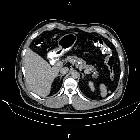

CT

CT features of chronic pancreatitis include:

- dilatation of the main pancreatic duct

- pancreatic calcification

- changes in pancreatic size (i.e. atrophy), shape, and contour

- pancreatic pseudocysts